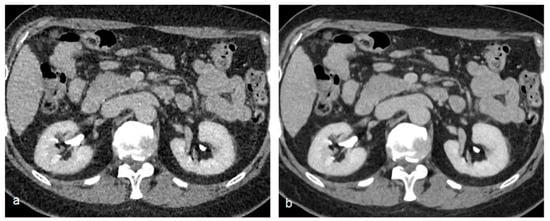

Figure 2.

Unenhanced (a) and arterial post-contrastographic phase (b) showing the presence of a right clear cell carcinoma (white arrows), isodense compared to the renal parenchyma in the unenhanced phase (a), and characterized by vivid contrast enhancement in the arterial phase (b).